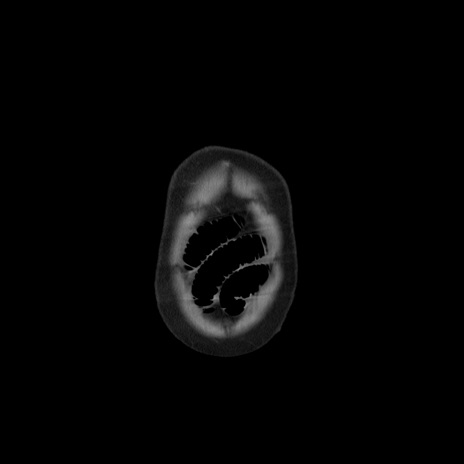

横断像